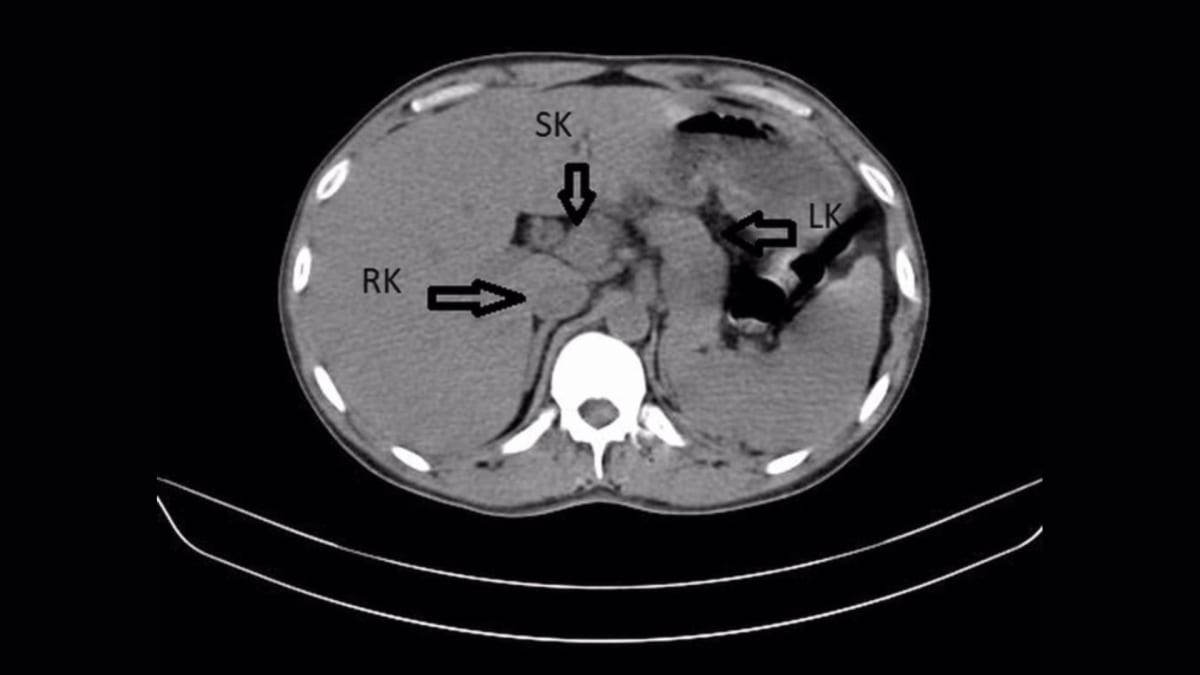

A 31-year-old man in India went to the doctor with a urinary tract infection and left with an astonishing discovery: he'd been living his entire life with an extra kidney.

Modern medical imaging revealed what his body had been hiding in plain sight for three decades.